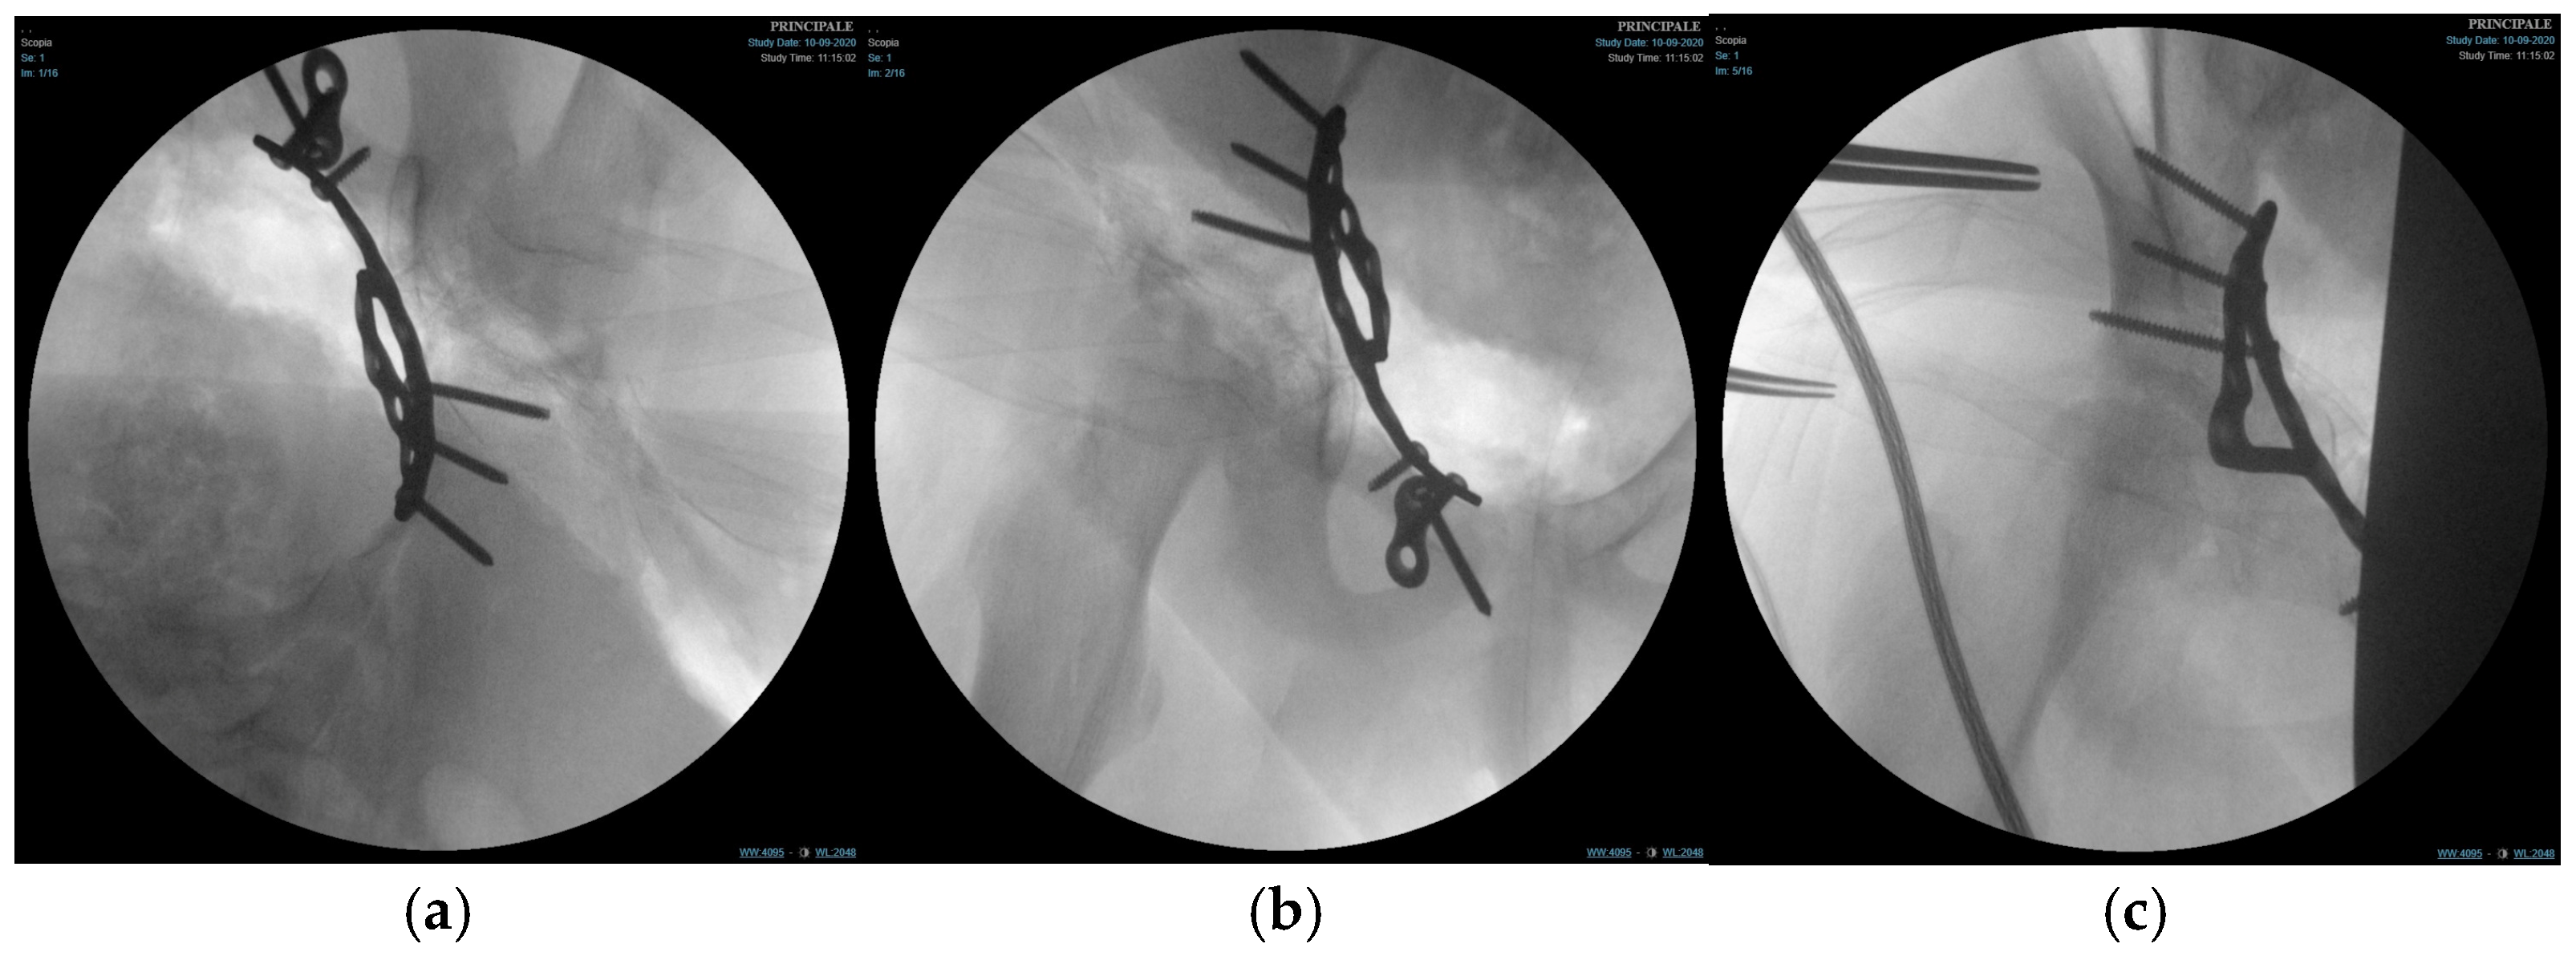

Subperiosteal dissection along the inner pelvis exposed the pelvic brim, anterior column, and quadrilateral surface. The transverse acetabular fracture and separation of the triradiate cartilage were visualised. Fracture reduction was achieved using a combination of pointed reduction clamps, ball-spiked pushers, and provisional K-wires (PRO Pelvis and Acetabulum System, Stryker, GmbH, Bohnackerweg 1 2545 Selzach, Switzerland) under fluoroscopic guidance (anteroposterior, iliac, and obturator oblique views) to restore the contour of the quadrilateral surface and ensure congruent reduction in the femoral head within the acetabulum.

Once an anatomical reduction was obtained, a 3D pre-contoured infrapectineal plate (PRO Pelvis and Acetabulum System, Stryker, GmbH, Bohnackerweg 1 2545 Selzach, Switzerland) was applied along the pelvic brim and quadrilateral surface to provide buttress support. The plate was fixed with multiple cortical screws placed in the supra-acetabular corridor and pubic ramus, avoiding penetration of the joint and the triradiate cartilage. The stability of fixation and joint congruency were confirmed fluoroscopically. (Figure 4) Wounds were irrigated and closed in layers over a drain.

Figure 4.

Fluoroscopic images of the surgical treatment of fracture of right acetabulum. (a) Iliac projection; (b) obturator view; (c) anteroposterior view.